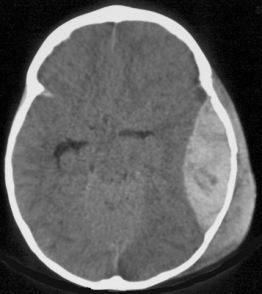

l’engagement temporal

il traduit la compression :

- du système d’éveil (réticulée activatrice ascendante du mésencéphale et diéncéphale)

- du mésencéphale et du noyau du III

- de la voie pyramidale

en conséquence, il se manifeste par :

- des troubles de conscience

- une mydriase homolatérale

- un déficit ou réaction de décérébration ou déficit contro-latéral

il provoque en outre une compression de l’artère cérébrale postérieure contre le bord libre de la tente du cervelet, à l’origine d’une ischémie (cf. ci-contre) avec comme conséquence une hémianopsie latérale homonyme.